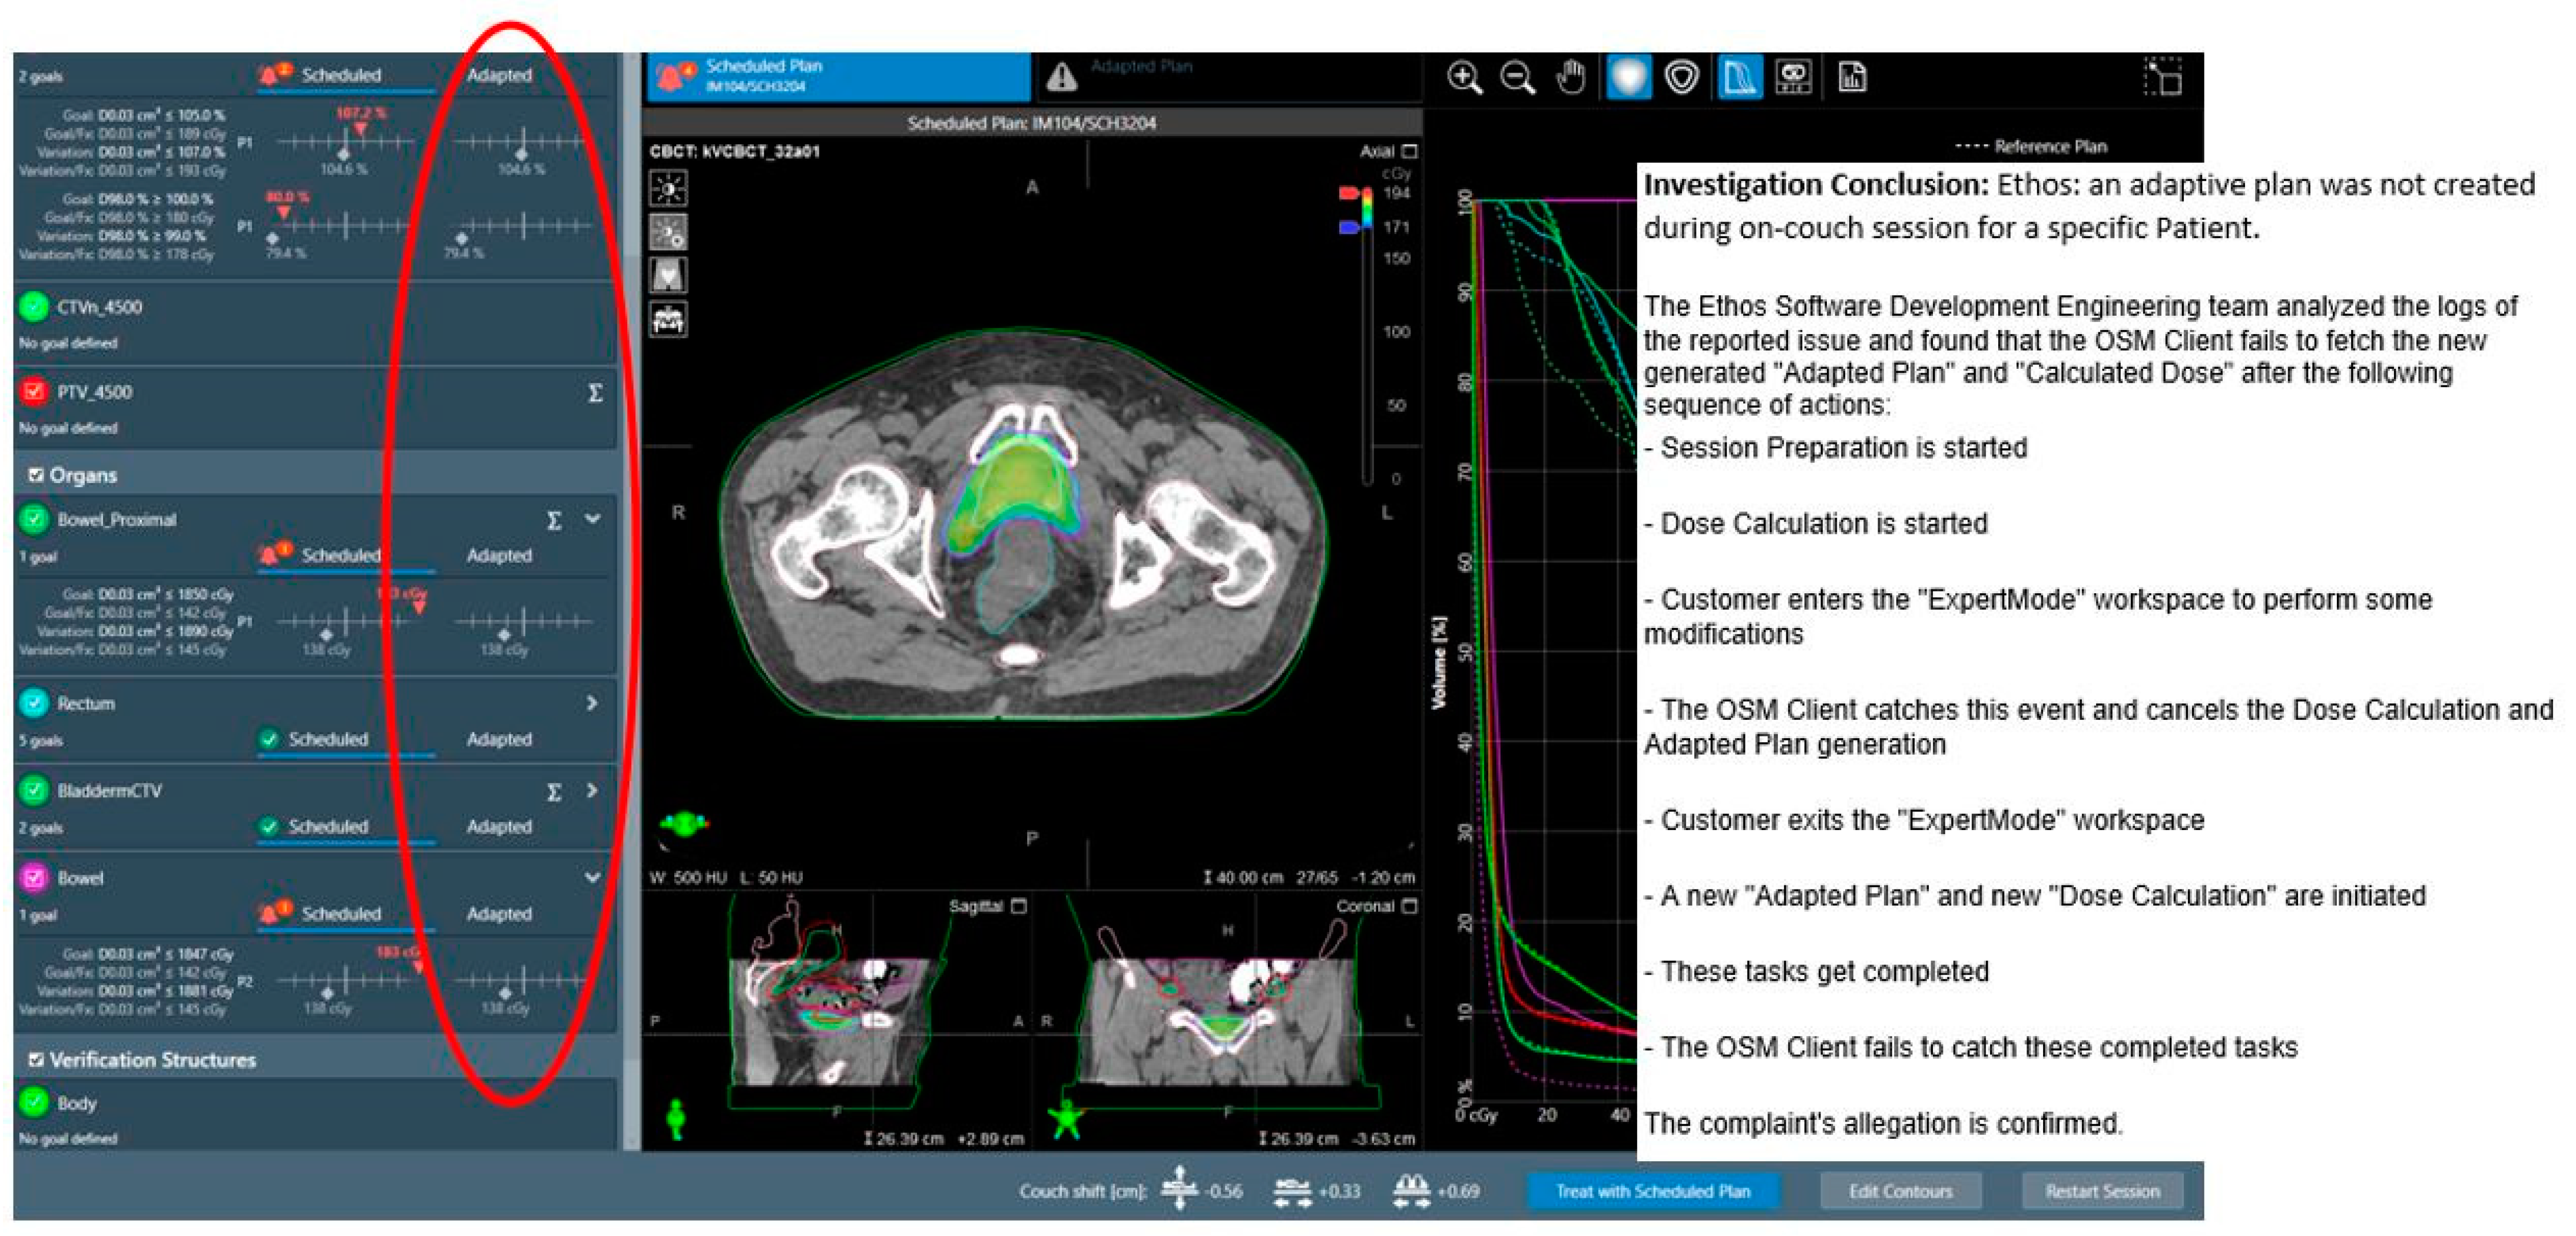

3.2.1. System-Driven Issues

| Adaptive plan unavailability due to internal software communication issues | 0.1% (1 instance) | N/A |